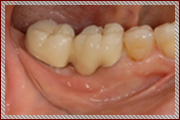

― 治療後 ―

計画した位置に正確に施術することで良好な審美結果が得られます